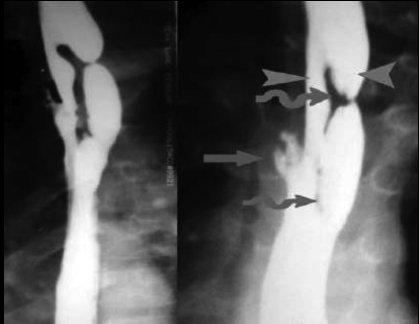

| images TOGD de oesophage

normale |

image TOGD de oesophage (

angle de His ) et estomac normale |

Images normales de estomac , bulbe et

duodenum expose en serie |